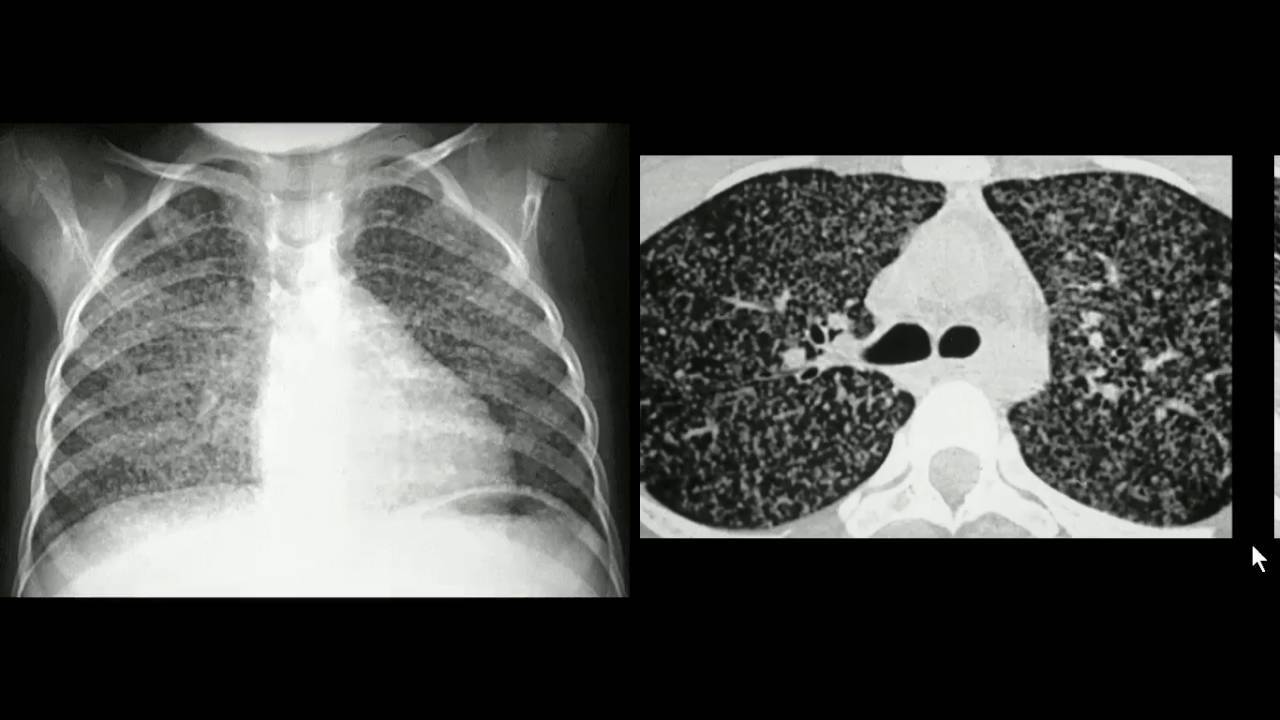

Voltinha pelo corpo… (Fígado, SNC… pulmão novamente, por via sanguínea): TB Miliar! (Não está nos alvéolos)

Geralmente ocorre nos imunodeprimidos e crianças.

TB Miliar.